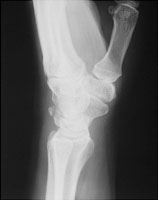

Triquetral fractures are usually best seen on the lateral radiograph of the wrist. Most of these fractures are dorsal avulsion fractures at the attachment of the radiocarpal ligament. The mechanism of injury is forced hyperflexion.

- Click on the image for a larger versionALateral radiograph of the hand. This shows a small bone fragment located dorsally. This a fractured triquetrum.